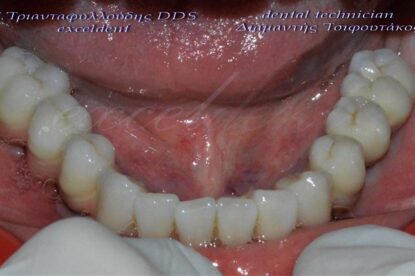

Ακόμη ένα περιστατικό ολικής στοματικής αποκατάστασης ασθενούς με ακίνητες γέφυρες στηριζόμενες σε εμφυτεύματα(8 στην άνω και 7 στην κάτω γνάθο).

Η συγκεκριμένη ασθενής είχε κατά το παρελθόν κατασκευάσει πλήθος οδοντοστοιχιών(μασέλες), τις οποίες απέρριπτε καθώς είχαν ελλιπή συγκράτηση και της δημιουργούσαν αντανακλαστικό εμέτου.

Με τις νέες ακίνητες αποκαταστάσεις επανήλθε τόσο η αυτοπεποίθηση και η άνεση της ασθενούς όσο και η μασητική της ικανότητα στα προ της απώλειας των δοντιών της επίπεδα.